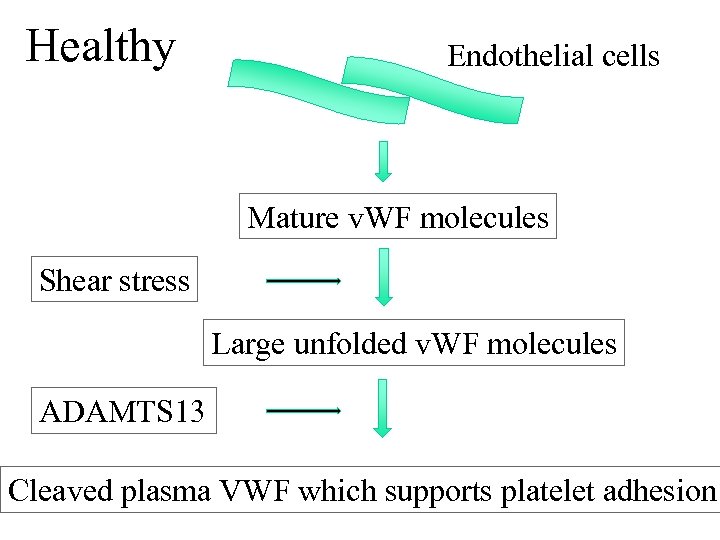

HUS/TTP • Aetiology • D+ verotoxin producing strain of E coli 0157 esp in children • D- sporadic form more commonly seen in adults. May be idiopathic or assoc with drugs, HIV and malignancy (infective diarrhoea not invariably associated) • Pathogenesis • ADAMTS 13 is a metalloproteinase which cleaves VWF to smaller subunits. Absence of or antibodies to this enzyme leads to build up of VWF multimers which promote platelet aggregation triggering MAHA • Presentation • Triad of ARF with MAHA and thrombocytopenia (HUS)

HUS/TTP • Aetiology • D+ verotoxin producing strain of E coli 0157 esp in children • D- sporadic form more commonly seen in adults. May be idiopathic or assoc with drugs, HIV and malignancy (infective diarrhoea not invariably associated) • Pathogenesis • ADAMTS 13 is a metalloproteinase which cleaves VWF to smaller subunits. Absence of or antibodies to this enzyme leads to build up of VWF multimers which promote platelet aggregation triggering MAHA • Presentation • Triad of ARF with MAHA and thrombocytopenia (HUS)

Healthy Endothelial cells Mature v. WF molecules Shear stress Large unfolded v. WF molecules ADAMTS 13 Cleaved plasma VWF which supports platelet adhesion

Healthy Endothelial cells Mature v. WF molecules Shear stress Large unfolded v. WF molecules ADAMTS 13 Cleaved plasma VWF which supports platelet adhesion